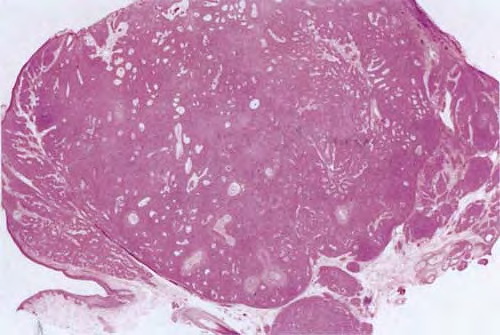

The term poroma refers to a group of rare cutaneous appendage tumors composed of cells (cuticular and poroid cells) similar to those of the acrosyringium. Poromas are traditionally subcategorized histopathologically based on their location in relation to the epidermis into three main variants; namely, hidroacanthoma simplex, eccrine poroma, and dermal duct tumor. Some authors add poroid hidradenoma to this group. There are also reports of “poromas” with differentiation toward the folliculosebaceous-apocrine unit.

Hidroacanthoma simplex shows sharply demarcated aggregations of cuboid to ovoid cells confined to the epidermis. Eccrine poroma reveals aggregations of uniform basaloid cells that radiate from the basal layer of the epidermis into the dermis . Dermal duct tumor consists of several sharply circumscribed, mainly dermal nodules composed of poroid and cuticular cells. Ductal structures are frequently observed. Poroid hidradenoma is characterized by intradermal, solid, and cystic aggregations of poroid cells.